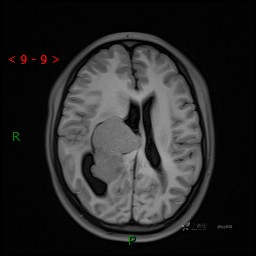

颅脑CT平扫

MRI平扫